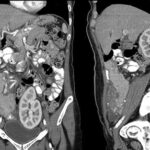

Fig. 3. Angio TC. Reconstrucción en 3D.

El contraste EV es importante para la detección y la evaluación de las complicaciones vasculares (angioTC) y para la documentación de la necrosis pancreática, que es la fase terminal de la lesión isquémica de la glándula. Se pueden hacer reconstrucciones en 3D que son muy útiles para el análisis conjunto con los cirujanos tratantes (Fig. 3) (3).